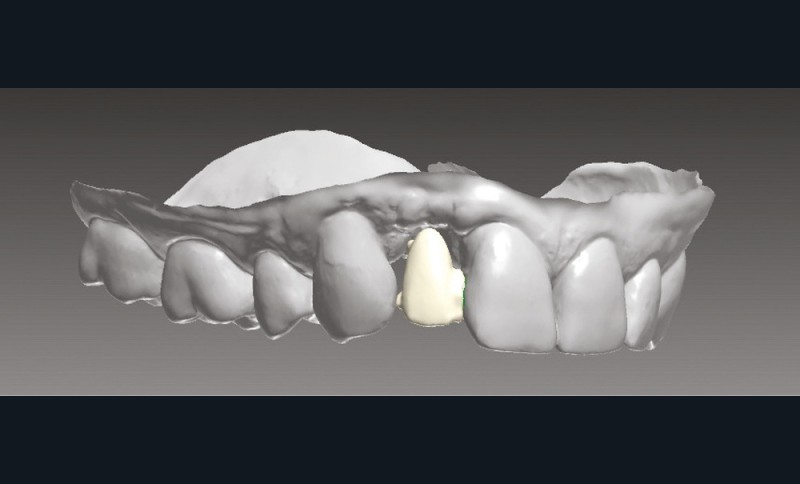

La situation clinique est transférée au prothésiste au moyen d’empreintes optiques (Trios 2, 3Shape) pour une conception numérique de la prothèse (fig. 8 et 9).

Phase de laboratoire

Une fois les modèles virtuels créés, l’armature du bridge est modélisée par Conception Assistée par Ordinateur sur le logiciel Trios Design Studio (3Shape) (fig. 10). La surface de connexion mesurée est de 9,8 mm2 (fig. 11) et celle de collage de 40,56 mm2, respectant ainsi les recommandations de la littérature [24].